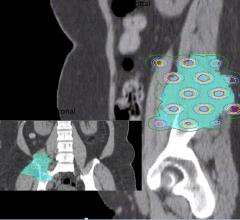

July 22, 2014 — Three teams of medical physicists are slated to make presentations about knowledge-based treatment ...

July 24, 2014 — Brainlab announced the release of its Elements automatic brain metastases planning software. The new ...